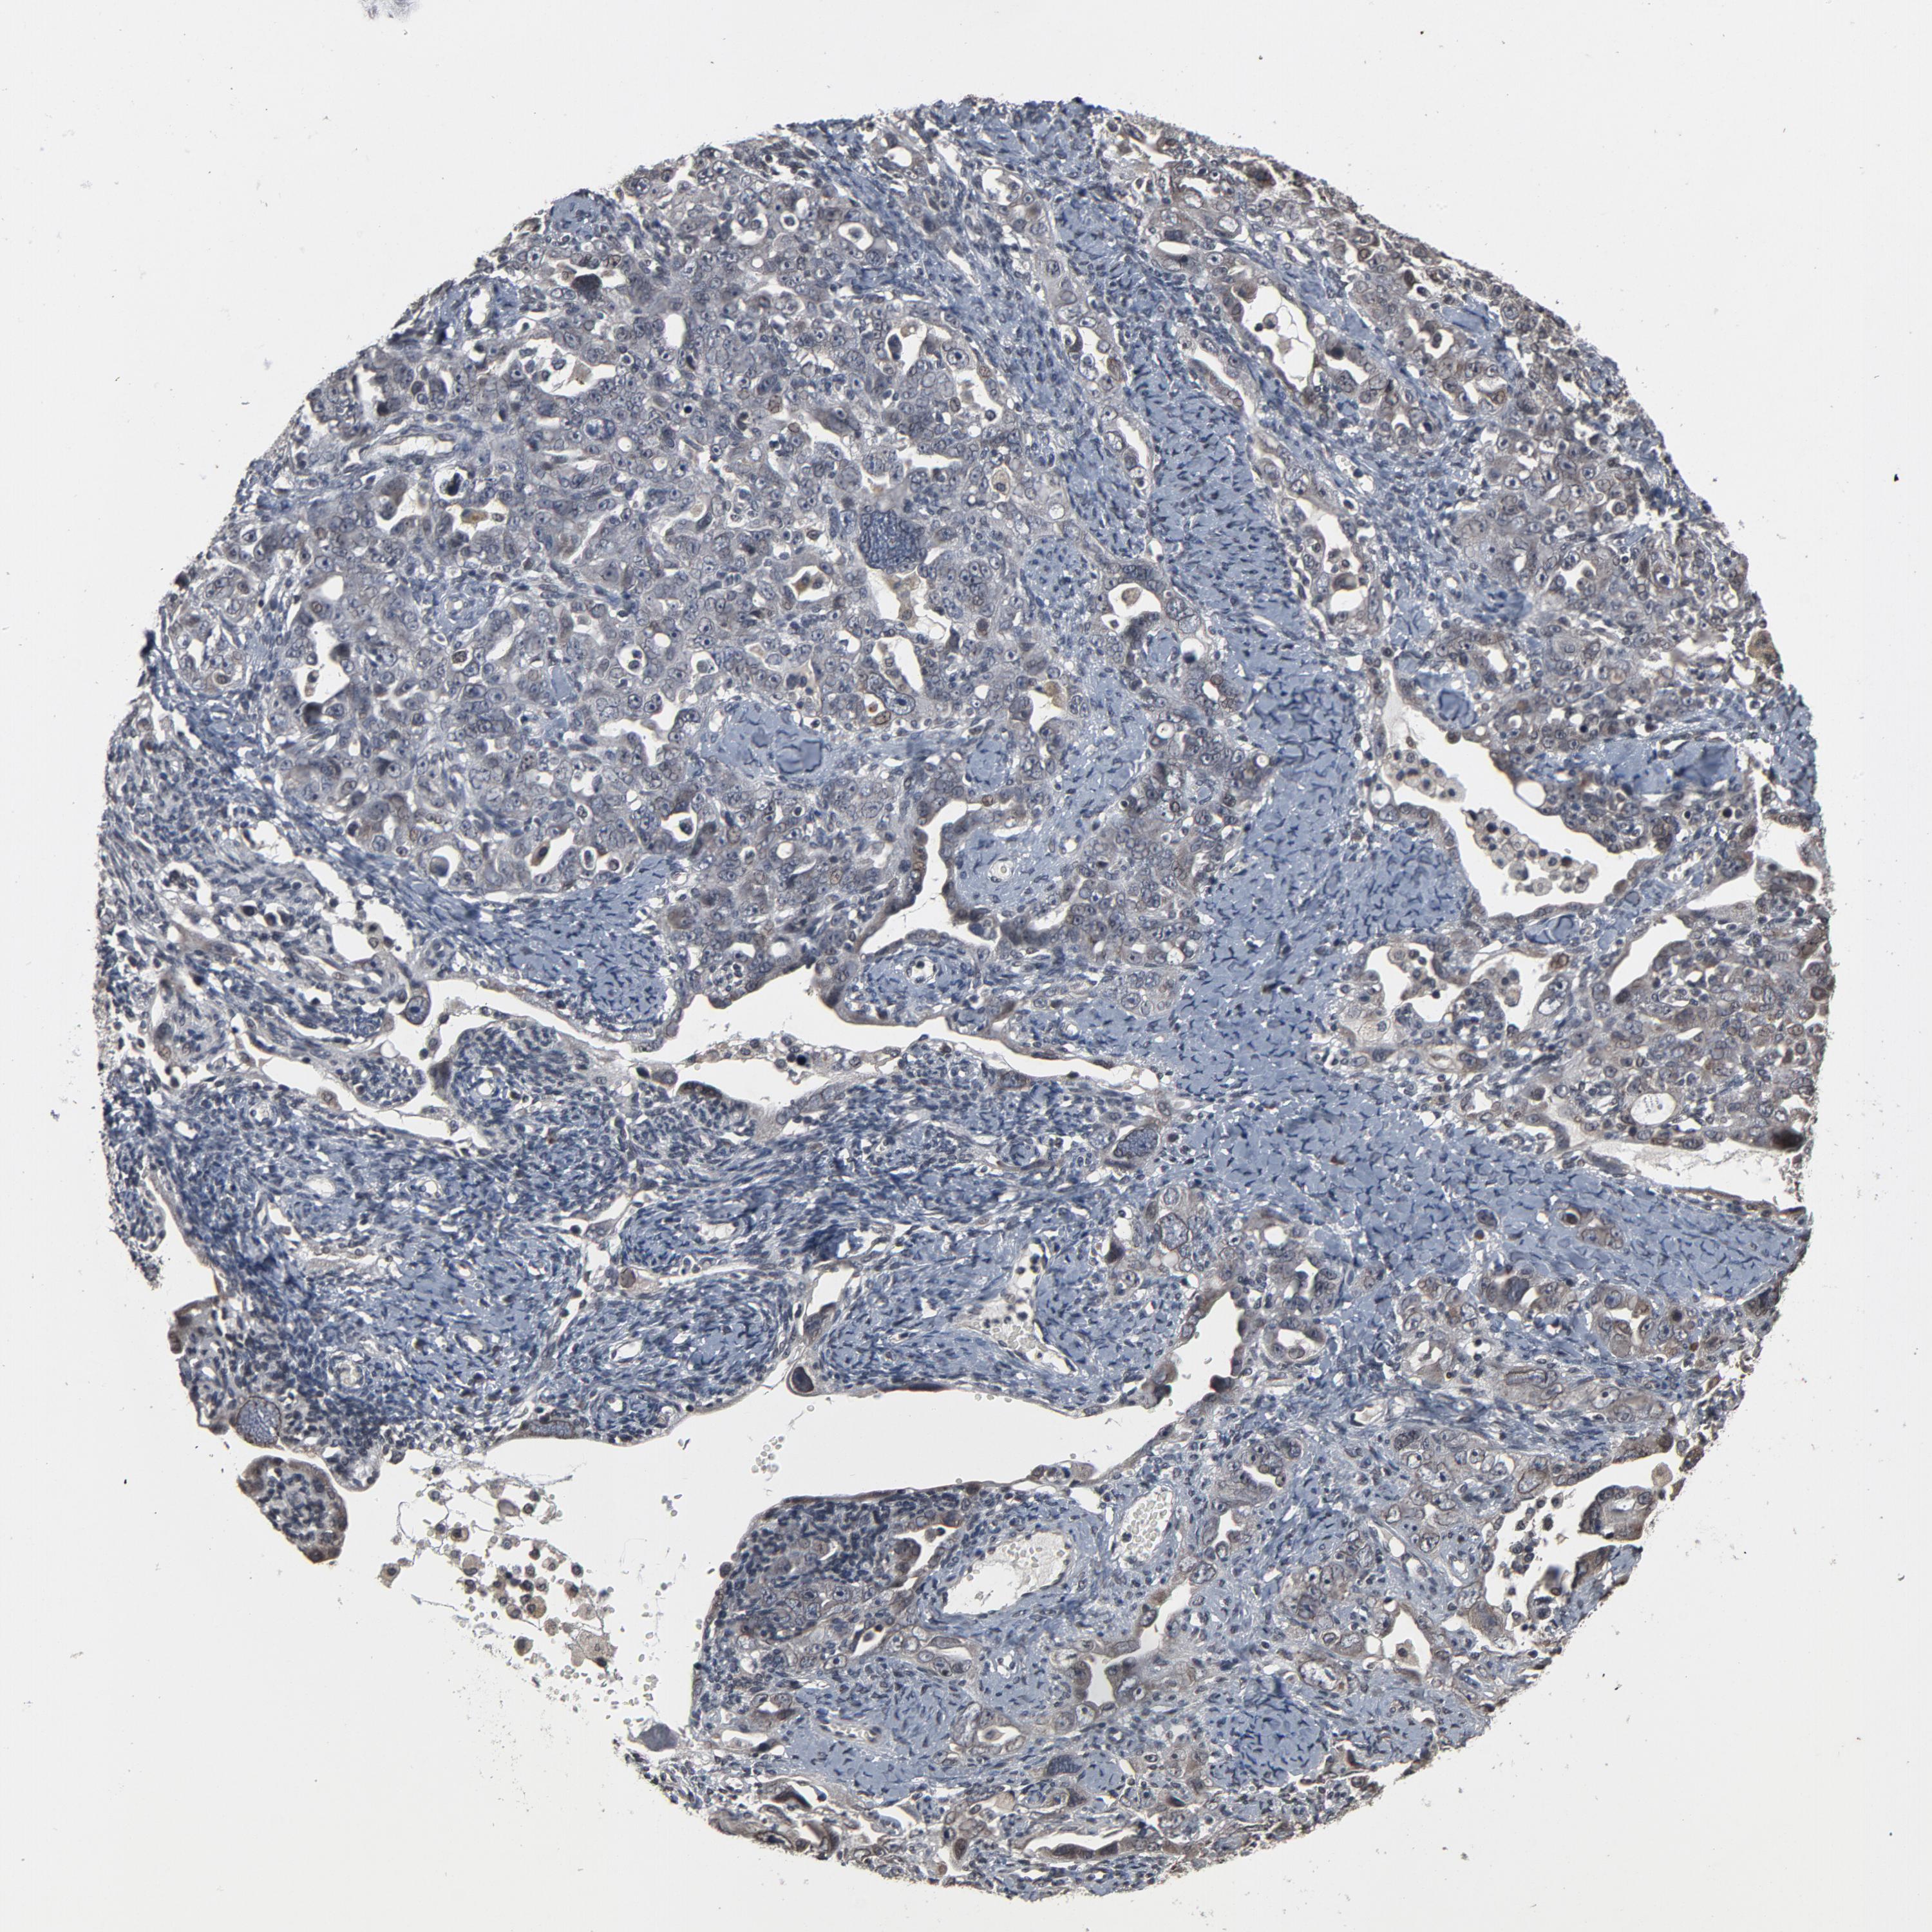

OVARIAN CANCER - Protein expressioni

A mouse-over function shows sample information and annotation data. Click on an image to view it in a full screen mode. Samples can be filtered based on level of antibody staining by selecting one or several of the following categories: high, medium, low and not detected. The assay and annotation is described here.

Note that samples used for immunohistochemistry by the Human Protein Atlas do not correspond to samples in the TCGA dataset.

Antibody stainingi

Antibody staining in the annotated cell types in the current human tissue is reported as not detected, low, medium, or high, based on conventional immunohistochemistry profiling in selected tissues. This score is based on the combination of the staining intensity and fraction of stained cells.

Each image is clickable and will lead to virtual microscopy that enables deeper exploration of all samples and also displays staining intensity scores, fraction scores and subcellular localization as well as patient and tissue information for each sample.

Antibody HPA049817

Cystadenocarcinoma, serous, NOS